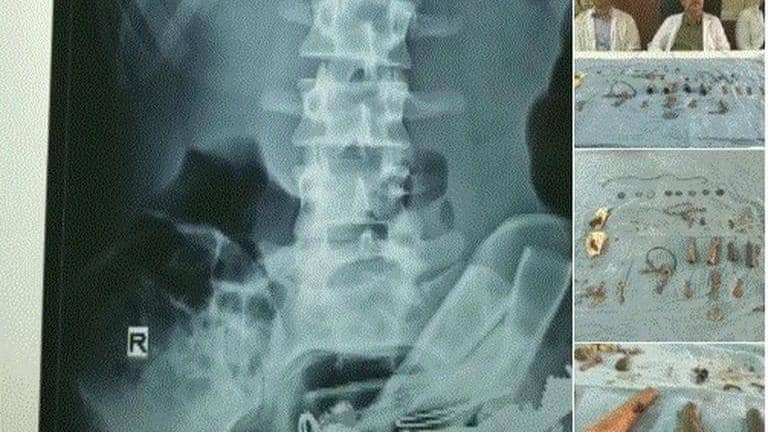

In an atypical case, doctors of a government hospital here have removed around 80 objects including "chillam", keys and coins from a mentally-ill patient's stomach in Udaipur on Monday. A team of four doctors conducted the operation which took 90 minutes.

"This could be considered a strange case. The man was admitted in the hospital complaining about a severe stomach ache. He was asked to undergo X-Ray. We were stunned to see small and big metal objects including nails inside his stomach," Dr DK Sharma told ANI.

Without any delay, doctors readied the patient for operation and removed the objects weighing in total 800 gm. Doctors discovered that the patient is mentally ill and an addict.

In a similar case last month, doctors had removed 116 nails, long wire and an iron pellet from the stomach of a 40-year-old man.